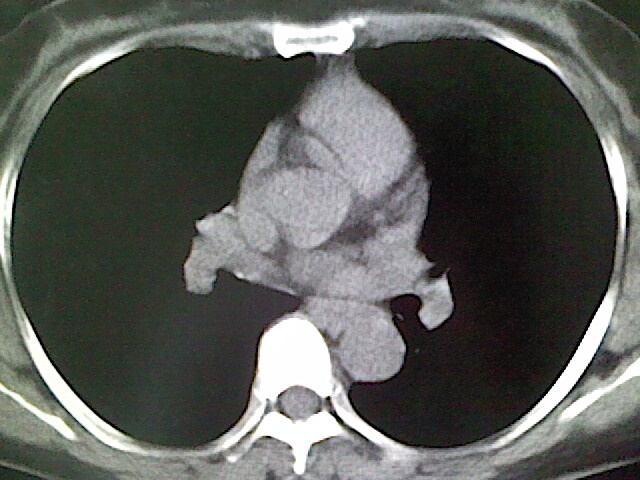

女,52岁,咳嗽,咳痰多日

左下肺陈旧纤维索条!

左肺舌段炎性改变

我见过几例,为炎症后纤维条索

慢性炎症后改变

考虑慢性炎性病灶粘连牵拉改变。

左肺舌叶纤维锁条病变。

左肺上叶下舌段炎症并局部胸膜反应。

左肺舌叶纤维索条影。

左肺舌叶段陈旧性病变

左肺舌段炎性反应。片子的质量太不好了。

左肺舌段炎性

炎性改变

左肺舌叶纤维索条影